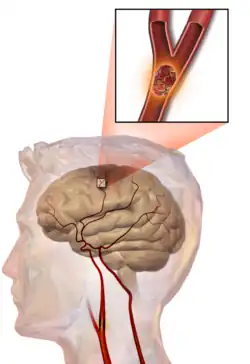

An embolic stroke refers to an arterial embolism (a blockage of an artery) by an embolus, a traveling particle or debris in the arterial bloodstream originating from elsewhere. An embolus is most frequently a thrombus, but it can also be a number of other substances including fat (e.g., from bone marrow in a broken bone), air, cancer cells or clumps of bacteria (usually from infectious endocarditis).[54]

Because an embolus arises from elsewhere, local therapy solves the problem only temporarily. Thus, the source of the embolus must be identified. Because the embolic blockage is sudden in onset, symptoms are usually maximal at the start. Also, symptoms may be transient as the embolus is partially resorbed and moves to a different location or dissipates altogether.

Emboli most commonly arise from the heart (especially in atrial fibrillation) but may originate from elsewhere in the arterial tree. In paradoxical embolism, a deep vein thrombosis embolizes through an atrial or ventricular septal defect in the heart into the brain.[54]